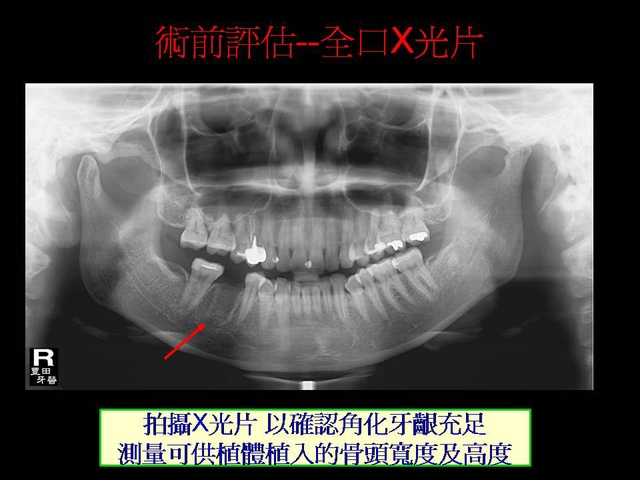

微創植牙介紹--pic介紹